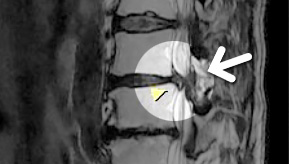

MRI

ϰ ڻ ͼ ̶ ؿ.

ü Ƶ ̰ ȣ µ

㸮 , ٸ ʹ

, Ƹ, ߰ ļ

ũ Ŀ

MRI ġ